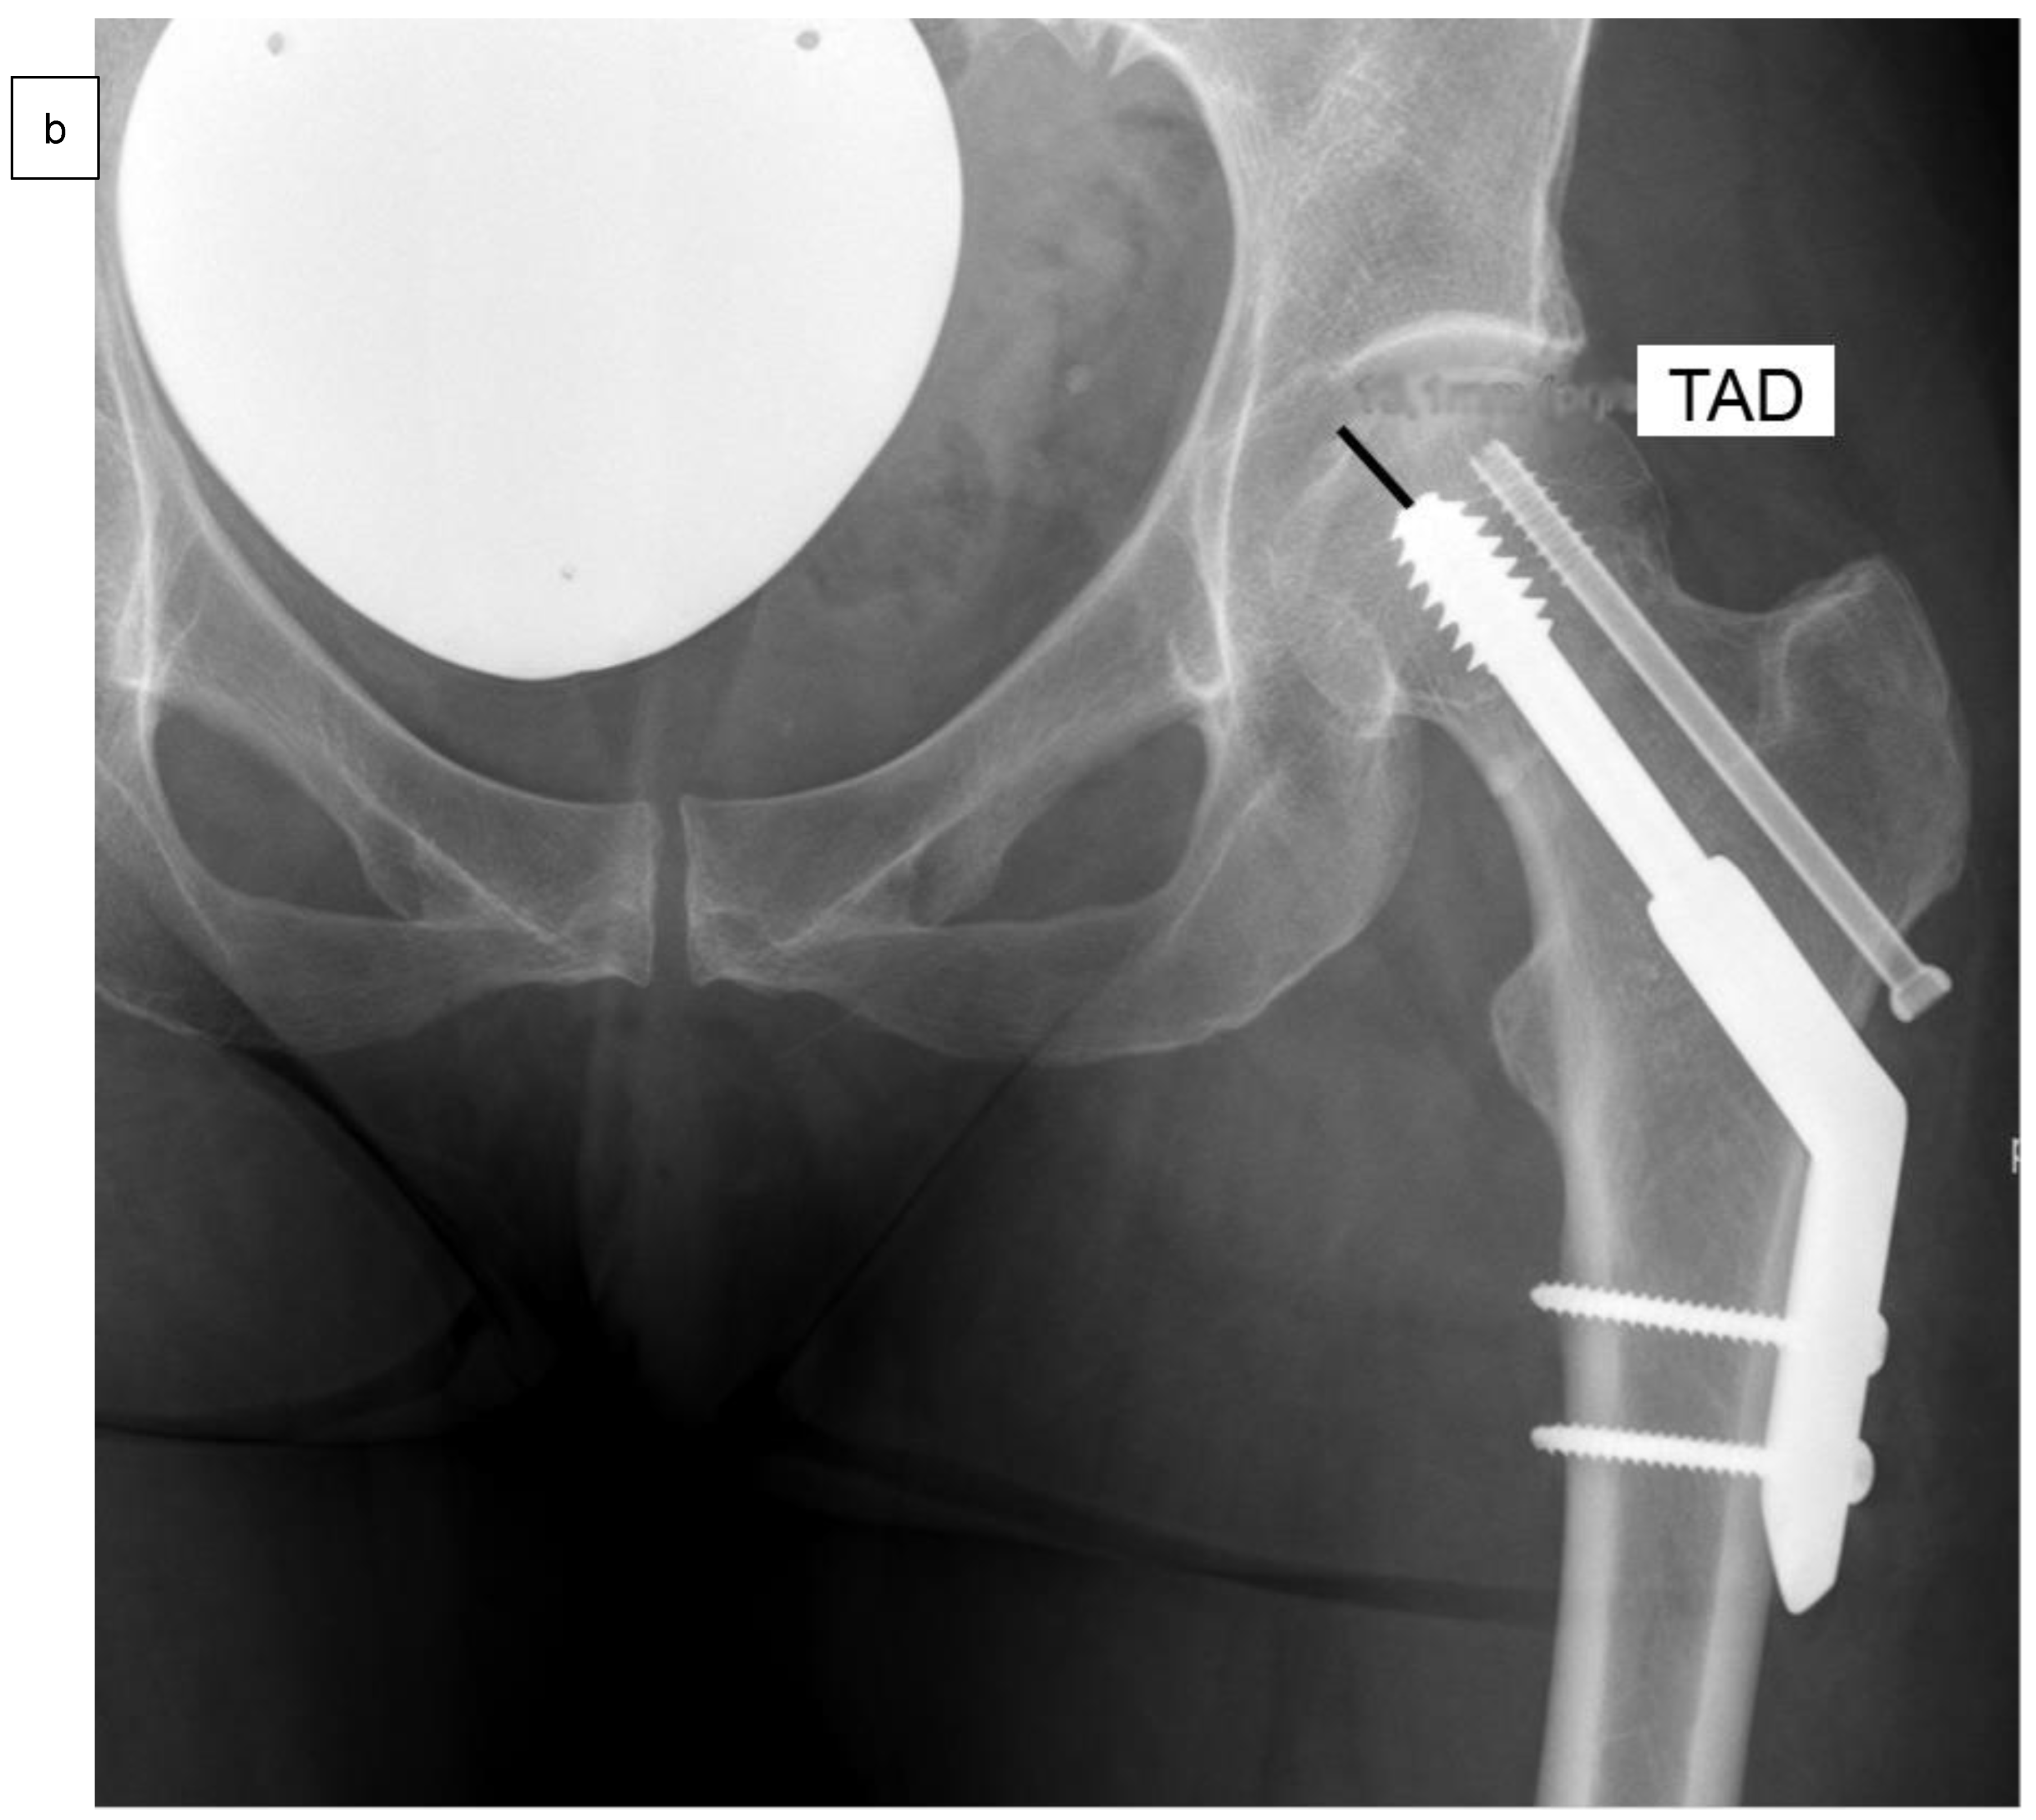

| Tip-apex distance (TAD) | 10.0 ± 2.9 mm | 9.3 ± 2.8 mm | 0.89 |